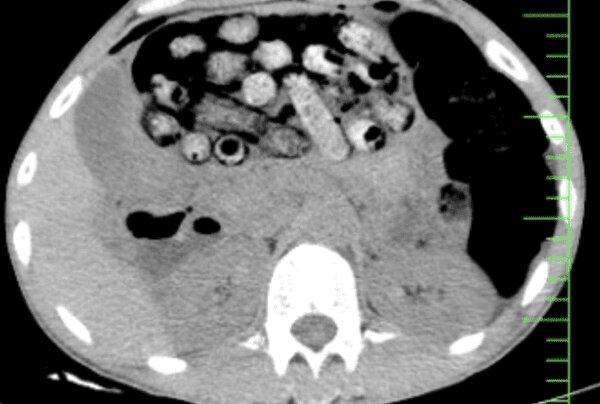

بر اساس اظهارات مأمور همراه، این فرد پیش از مراجعه اقدام به بلع تعدادی بسته محتوی مواد مخدر کرده بود که در پی انجام تصویربرداری، تعداد زیادی بسته مشکوک در معده و روده کوچک و بزرگ وی مشاهده شد.

با توجه به خطر پارگی احتمالی بستهها و احتمال بروز عوارض تهدیدکننده حیات، بیمار بلافاصله به اتاق عمل منتقل شد و جراحی سنگینی از ساعت ۳ بامداد آغاز گردید.

این عمل جراحی به سرپرستی عضو هیأت علمی گروه جراحی عمومی دانشگاه علوم پزشکی البرز و با همکاری گروههای اورژانس، تصویربرداری، بیهوشی و جراحی انجام شد که درنهایت بیش از ۹۰ بسته مواد مخدر از معده و روده بیمار خارج شد.